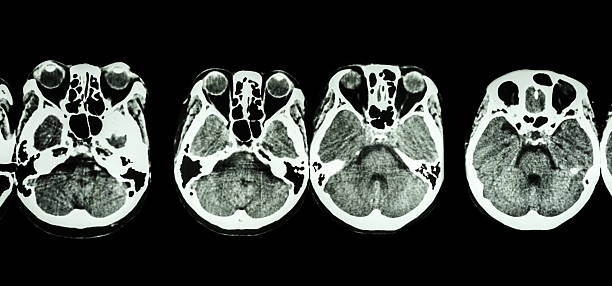

2. 두정엽 손상

두정엽 손상은 실인증과 관련이 있습니다. 환자는 물체를 만져보면 물체를 정확히 인식하지 못하거나, 반대편의 손으로 만졌을 때 자기 몸이 아닌 타인의 몸으로 인식할 수 있습니다.

3. 측두엽 손상

측두엽 손상은 기억력 저하, 청력 감소, 언어 기능 저하 등을 포함합니다. 이 증상은 혈관성 치매로 진행할 수 있으며, 가장 심각한 경우에는 실명에 이를 수도 있습니다.

4. 뇌관 부위 손상

뇌관은 우리 몸의 생체 징후를 담당하는 부위로, 이상이 있는 경우 음식을 적절히 소화하지 못하게 되어 식사에 어려움을 겪을 수 있습니다. 호흡 장애도 발생할 수 있어 인공호흡 장치가 필요할 수 있습니다.